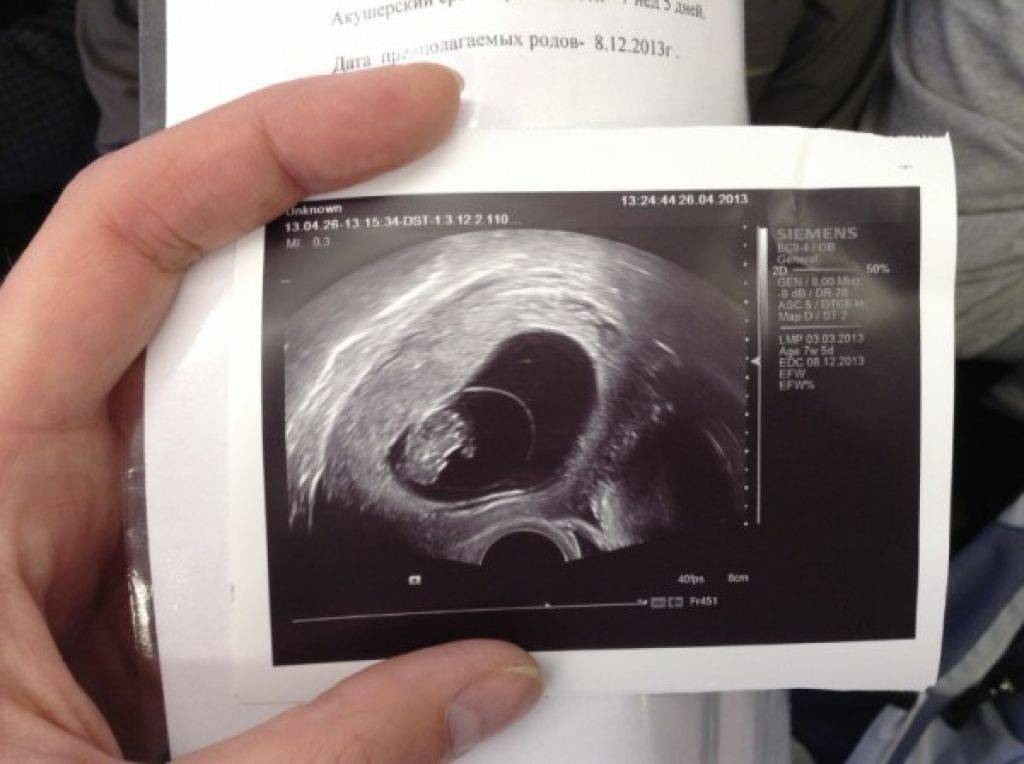

Развитие эмбриона на 8 неделе беременности